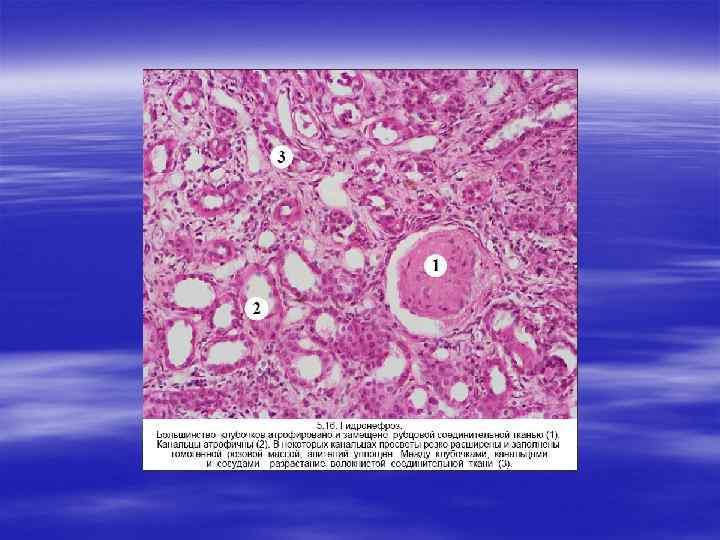

ГИДРОНЕФРОЗ § Гидронефроз представляет собой дилатацию почечной лоханки и чашечек, сопровождающуюся атрофией паренхимы. Основная причина гидронефроза — это обструкция мочевыводящих путей на любом уровне от уретры до почечной лоханки. Обструкция может быть внезапной или развиваться исподволь, врожденной или приобретенной, полной или частичной.

ВТОРИЧНЫЕ НЕФРОСКЛЕРОЗЫ § Поражение почек любой этиологии в итоге ведет к почечной недостаточности, структурной основой которой является нефросклероз. Нефросклероз представляет собой патологический про цесс, сопровождающийся разрастанием фиброзной ткани с уплот нением и сморщиванием почек. Поверхность почек приобретает зернистый или бугристый характер. В зависимости от причин выделяют две основные группы нефросклероза: первичное и вто ричное сморщивание почек.

§ Вторичное сморщивание почек развивается в исходе различных воспалительных, дистрофических и иммунопатологических процессов, развивающихся в них: § 1) хронических гломерулонефритов, § 2) хронического пиелонефрита, § 3) амилоидоза почек, § 4) мочека менной болезни, § 5) туберкулеза почек, § 6) диабетического гломерулосклероза.